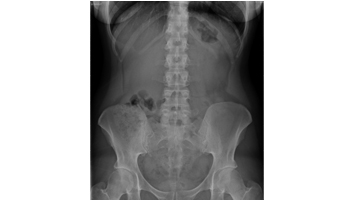

- Rx de l’abdomen : ASP/AUSP